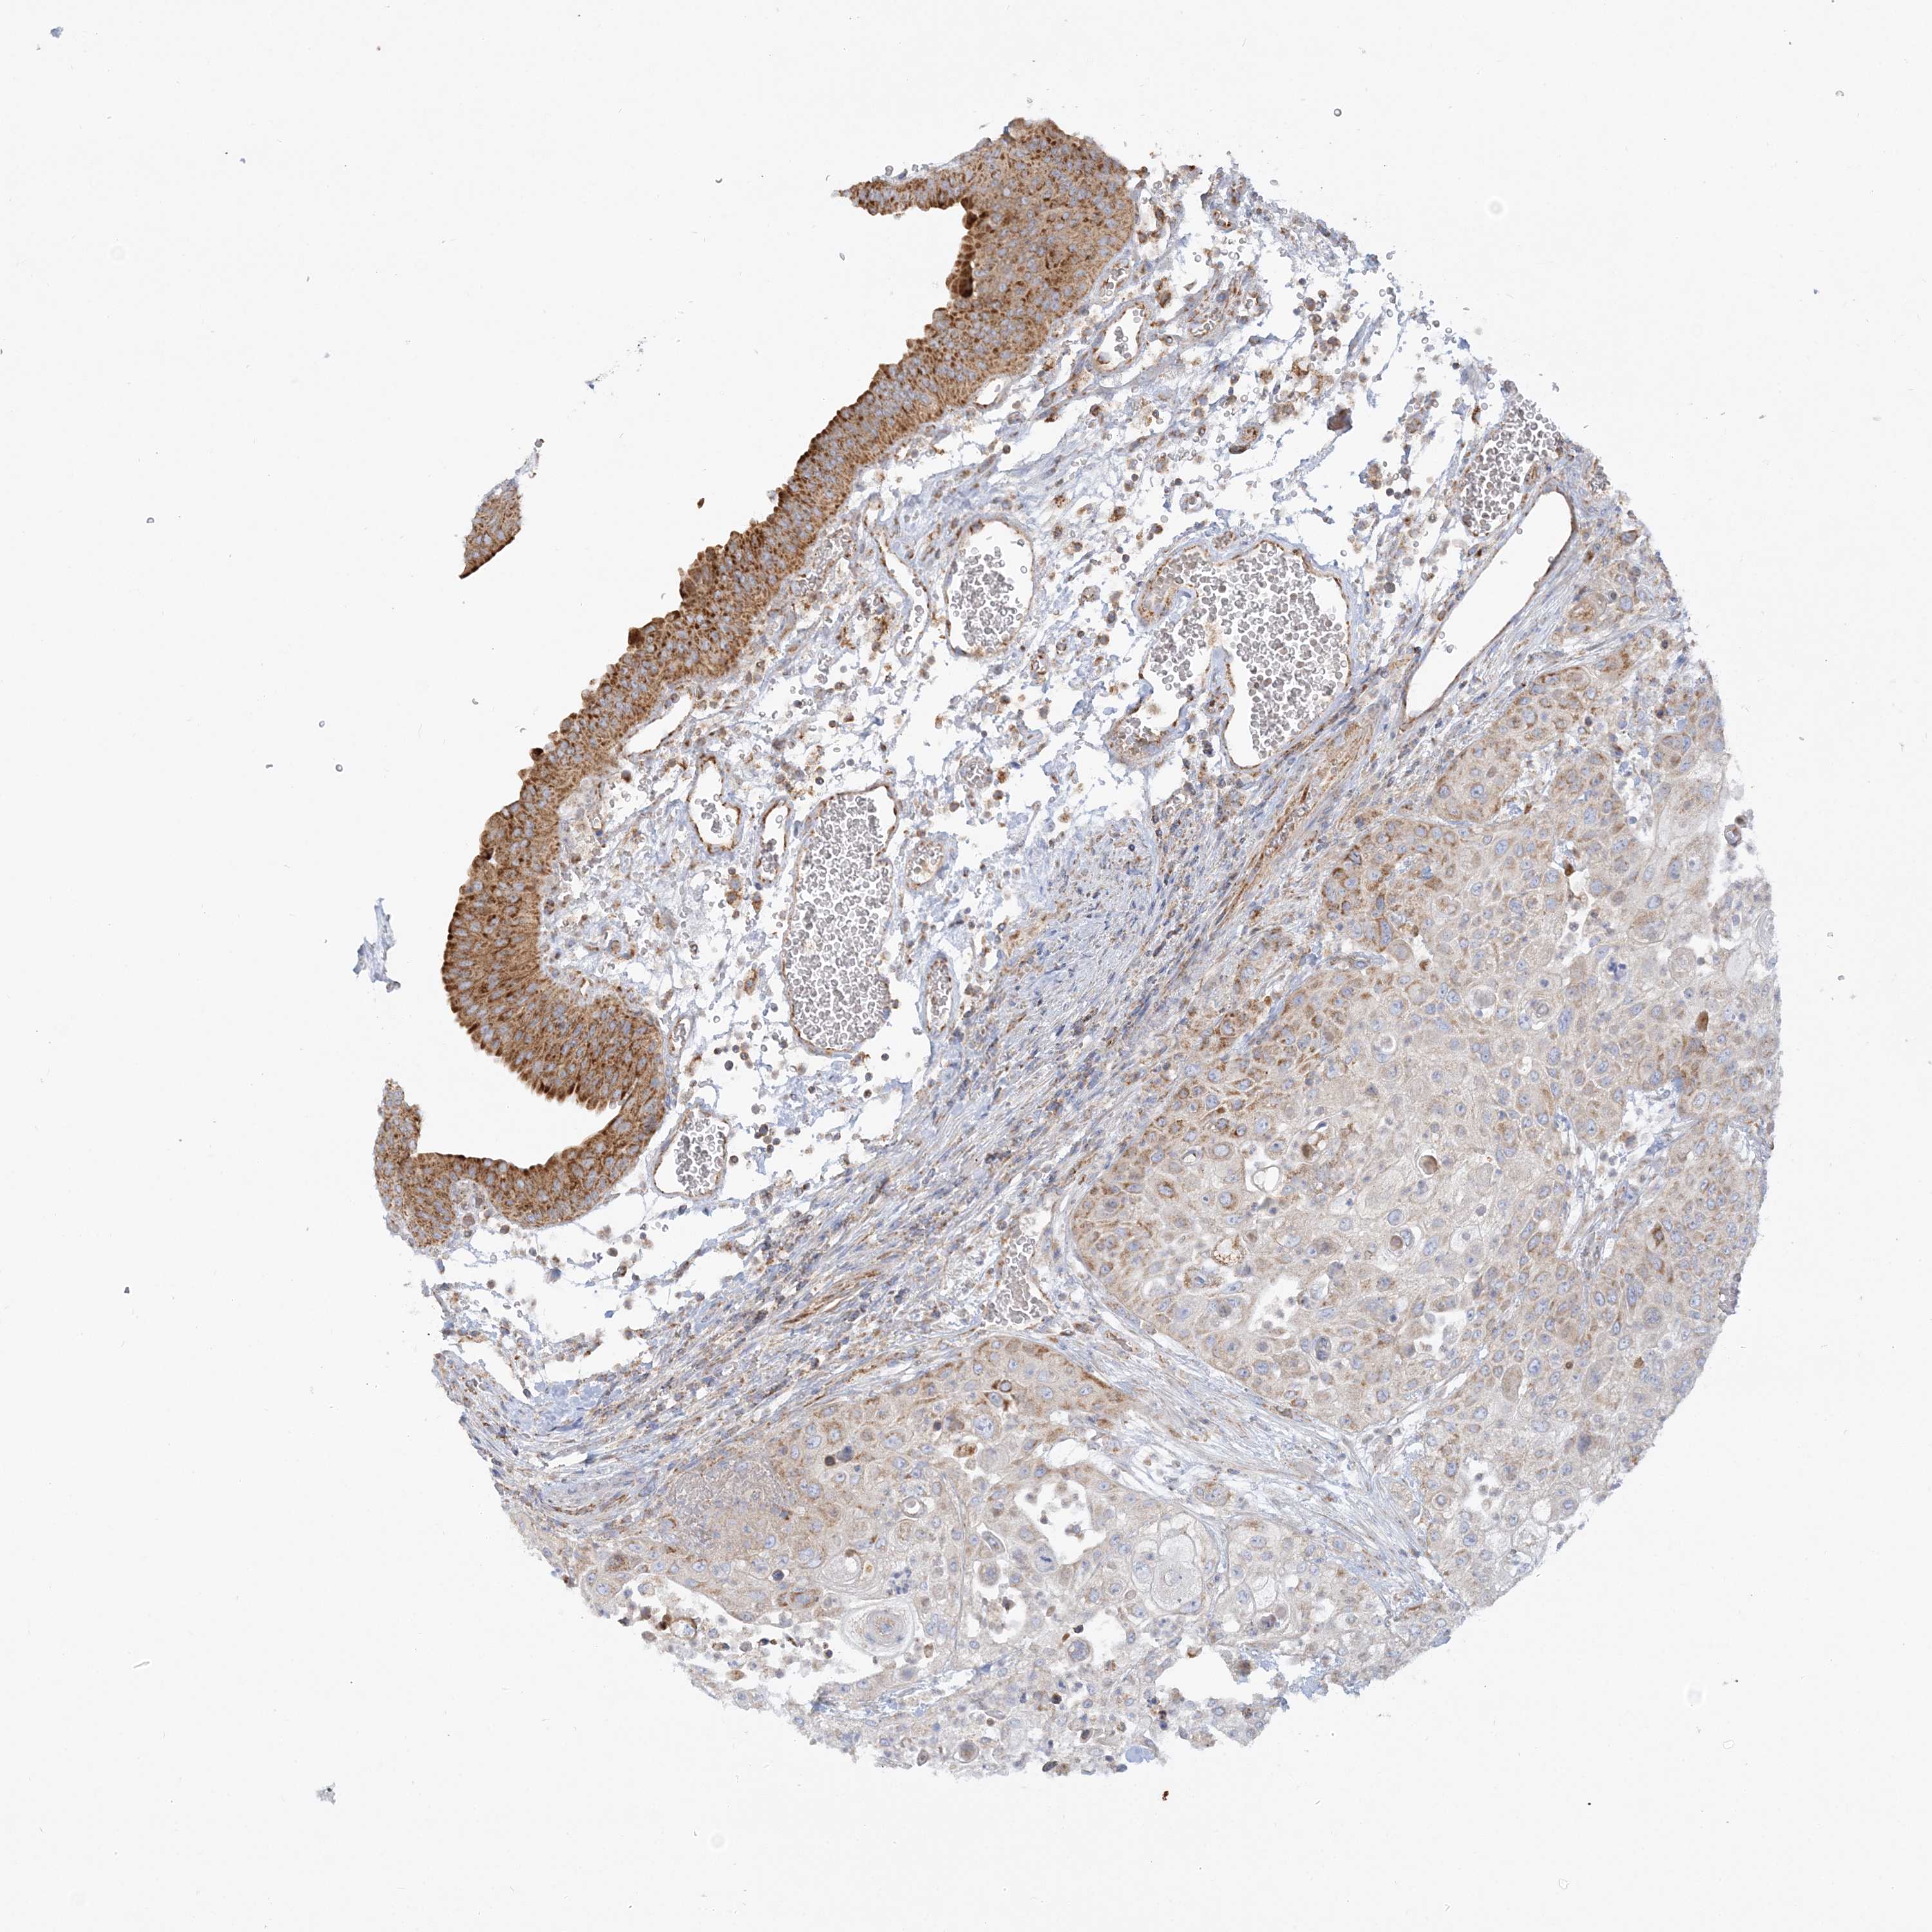

UROTHELIAL CANCER - Protein expressioni

A mouse-over function shows sample information and annotation data. Click on an image to view it in a full screen mode. Samples can be filtered based on level of antibody staining by selecting one or several of the following categories: high, medium, low and not detected. The assay and annotation is described here.

Note that samples used for immunohistochemistry by the Human Protein Atlas do not correspond to samples in the TCGA dataset.

Antibody stainingi

Antibody staining in the annotated cell types in the current human tissue is reported as not detected, low, medium, or high, based on conventional immunohistochemistry profiling in selected tissues. This score is based on the combination of the staining intensity and fraction of stained cells.

Each image is clickable and will lead to virtual microscopy that enables deeper exploration of all samples and also displays staining intensity scores, fraction scores and subcellular localization as well as patient and tissue information for each sample.

Antibody HPA036930

Staining

High

Medium

Low

Not detected

Intensity

Strong

Moderate

Weak

Negative

Quantity

>75%

75%-25%

<25%

None

Location

Nuclear

Cytoplasmic/membranous

Cytoplasmic/membranous,nuclear

Urothelial carcinoma, High grade

Urothelial carcinoma, Low grade